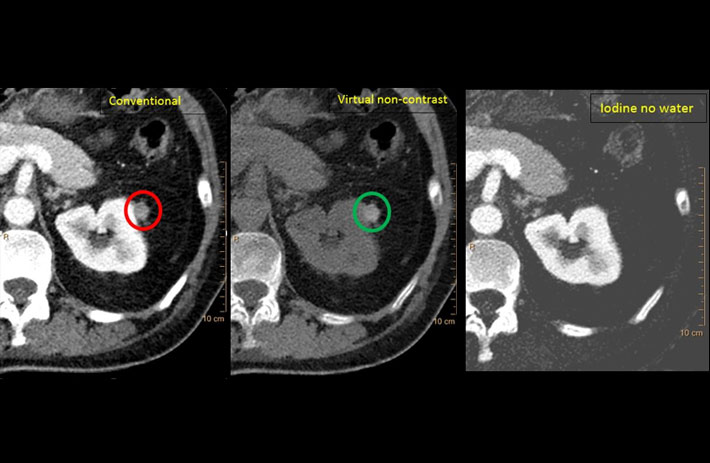

Mit dem Spektral-Detektor-CT werden Spektraldaten automatisch bei jedem Scan erfasst. Die Informationen stehen jederzeit auf der Scankonsole, der CT-Workstation sowie an jedem PACS-Arbeitsplatz zur Verfügung, sodass es nicht notwendig ist, den Patienten erneut zu scannen, bspw. wenn initial zufällige Anomalien festgestellt wurden. Dadurch profitieren Anwender durch eine höhere Diagnosesicherheit und weniger Nachuntersuchungen auf anderen bildgebenden Systemen. Unsere Fallsammlung zeigt, welchen klinischen Mehrwert der Spektral-Detektor-CT in unterschiedlichsten Anwendungsbereichen in der klinischen Routine bringt. Jede Woche gehen neue Fälle live.